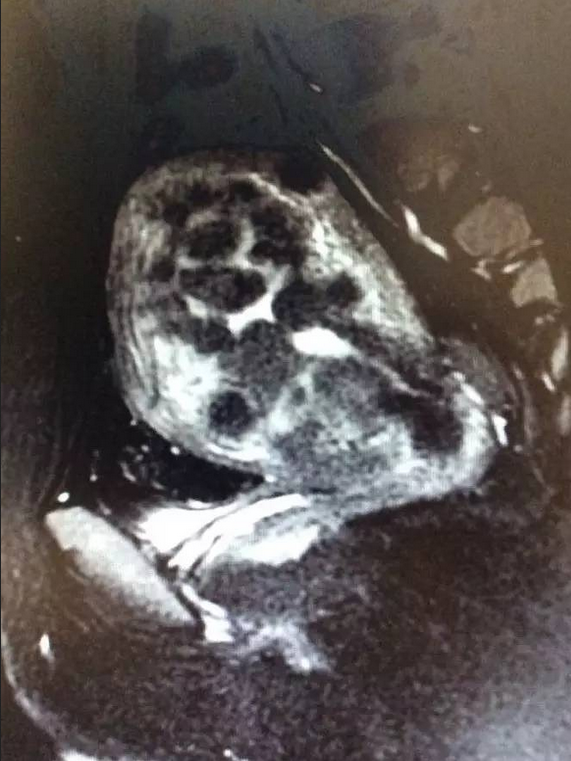

图4. T2高信号的肌瘤

(5)病灶的信号,子宫肌瘤随着肌瘤内部的水分含量不同,在核磁共振的T2影像学会有不同的表现,短T2的肌瘤在图片上通常看起来是黑影的,瘤子内部含水分比较少,超声波能量容易蓄积,造成肌瘤内热量的快速上升;而长T2信号的肌瘤在图像上看起来颜色偏白,水分含量比较高,不太容易治疗成功(有点象湿的柴火不太容易点着)。